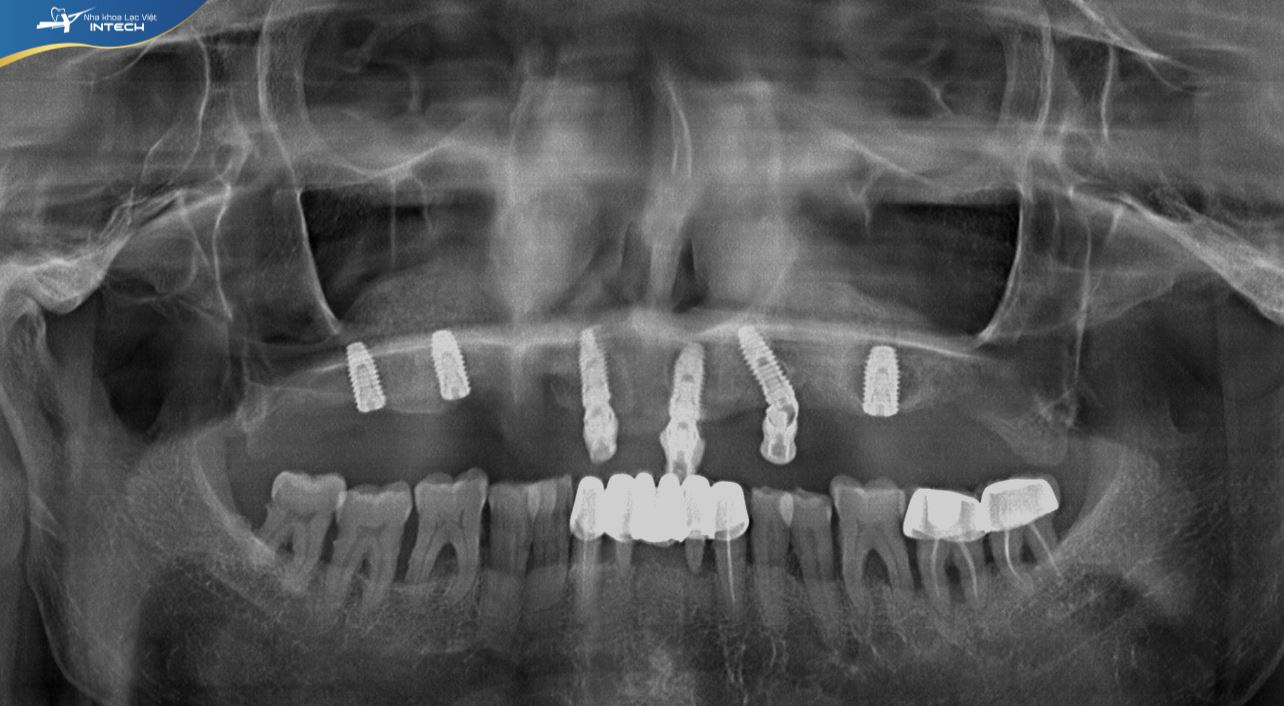

Qua thăm khám và chụp phim X-quang, bác sĩ đã đưa ra chẩn đoán về tình trạng trước của chú Phương:

• Làm cầu răng sứ sai cách, răng đã điều trị tủy

• Hàm trên mất nhiều răng, chỉ còn răng 24

• Hàm dưới làm cầu sứ các răng cửa

• Sai lệch khớp cắn, xương hàm bị tiêu biến nhiều

• Nướu bị sưng viêm, đau nhức, khả năng ăn nhai kém

Kế hoạch điều trị của bác sĩ Hoàng Vũ Hiệp - Bác sĩ phụ trách cấy ghép Implant case của chú Phương đưa ra đó là:

• Nhổ bỏ toàn bộ các răng không còn chức năng ở hàm trên

• Phục hình toàn bộ răng hàm trên bằng phương pháp Implant All On 6

Quá trình cấy ghép Implant diễn ra đúng theo kế hoạch điều trị ban đầu. Các trụ Implant sau khi cấy vào xương hàm tích hợp ổn định, bác sĩ cũng lắp hàm tạm cho bệnh nhân để đảm bảo chức năng ăn nhai.

Hình ảnh phim chụp X-quang của chú Phương sau khi trồng Implant All On 6Hình ảnh phim chụp X-quang của chú Phương sau khi trồng Implant All On 6